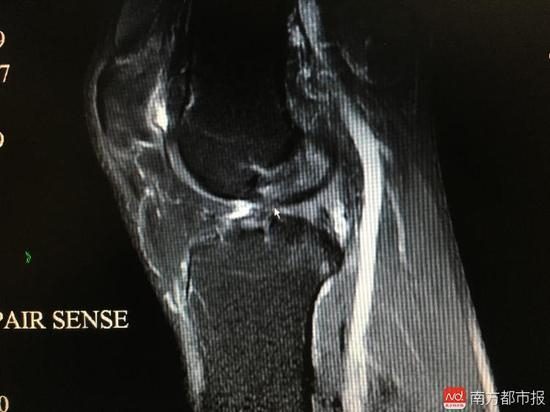

在尝试了换跑姿,戴护膝、针灸等各种理疗后,还是没什么效果。赵先生来到了广州南医三院关节外科·运动医学科就诊。蔡道章为其查体的时候,一拉他的左腿,说应该是前叉断了。拍了核磁共振确认后,赵先生都不敢相信,这么多年了才检查出来,“很懊悔,觉得对自己很不负责任”。